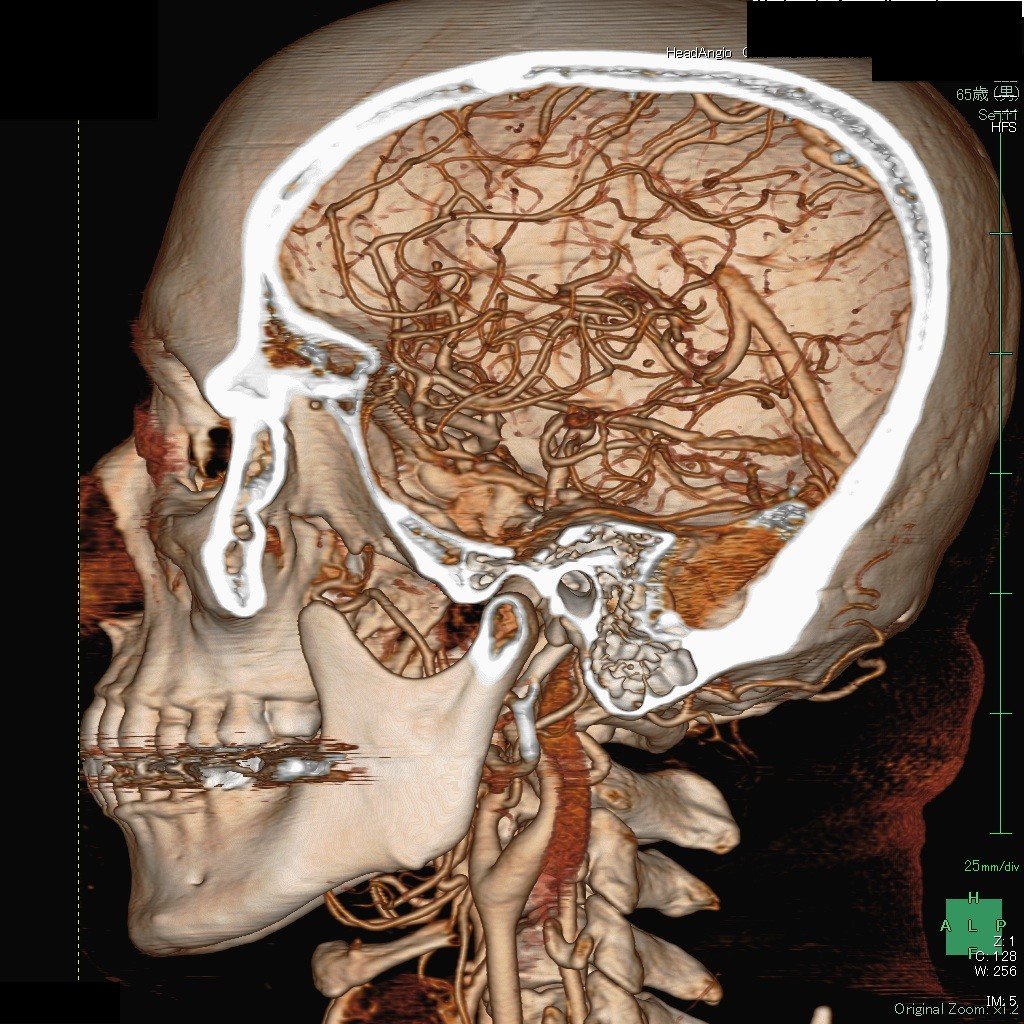

これは、造影剤を使って脳内の動脈を3Dで撮影した画像(3D-CTA)です。患者さんに説明するときにも、画面でmovieとしてお見せできます。

たとえば、このYouTubeの画像は私が血管内治療をする直前の3D-CTAの画像(動画)です。

さらに、この3DーCTA画像は骨をどこで切り取るかによって色々な画像を作る事ができます

また、頭蓋骨ごと回転させて、頚部動脈も観察する事ができます